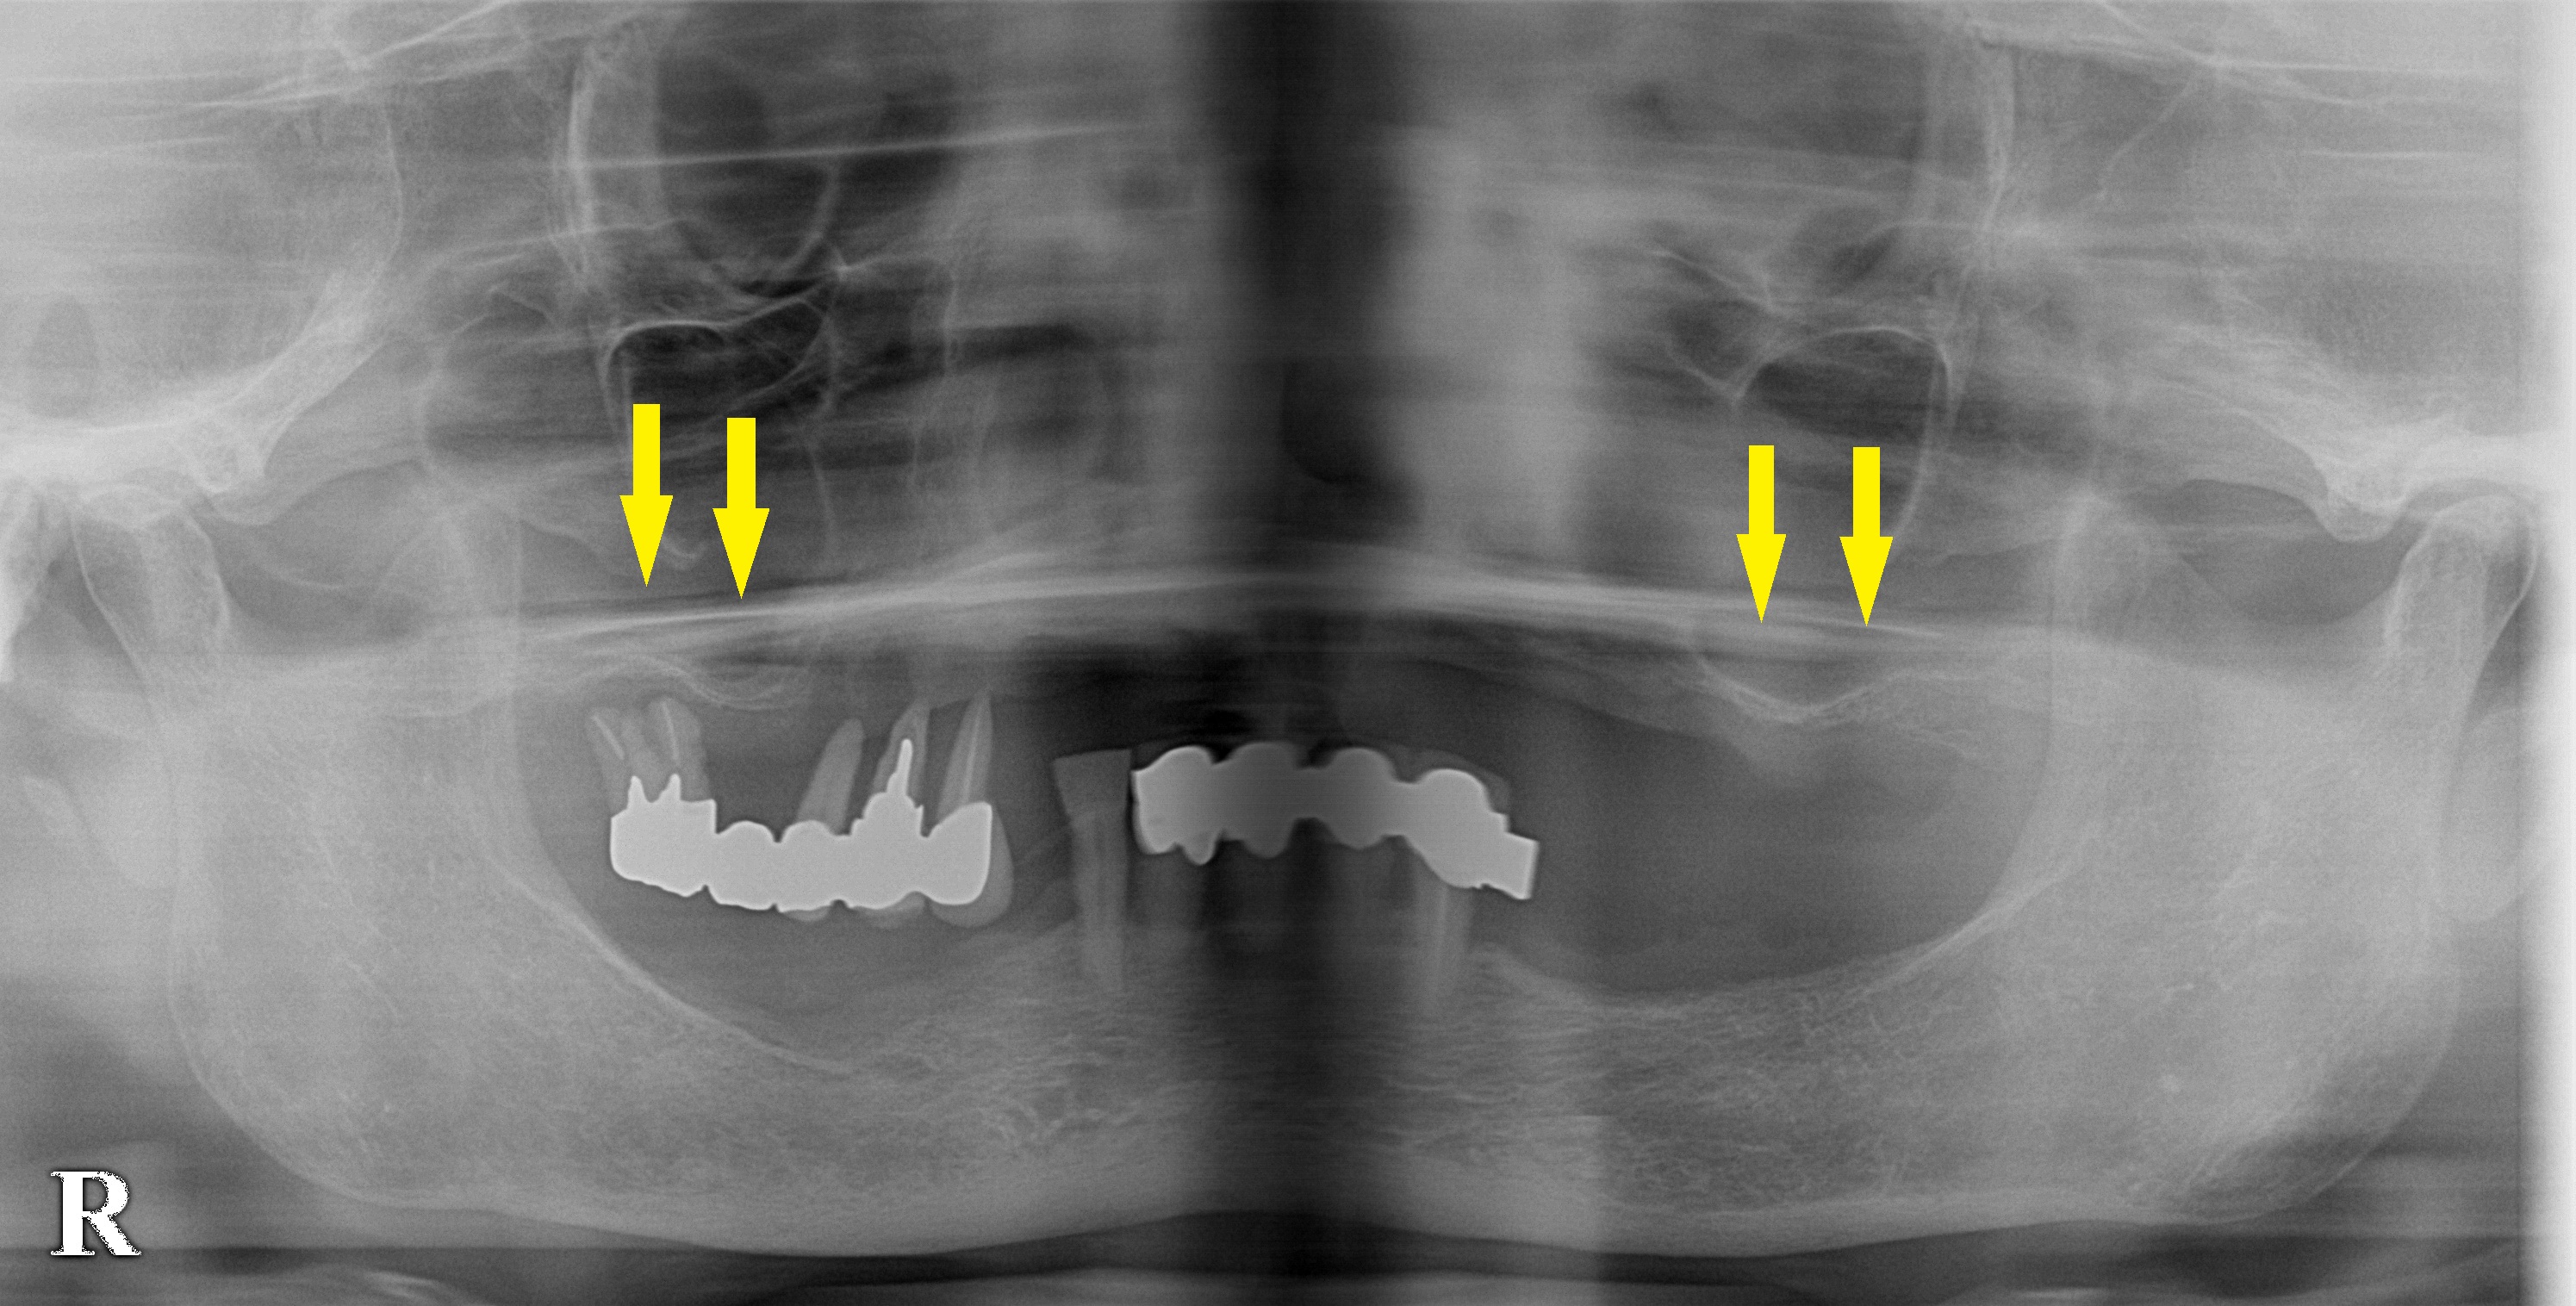

レントゲン、CTを撮影すると、上顎臼歯部は、本当に骨が薄くて、インプラント埋入も困難な状態でした(上段写真、下段左写真)。

それでも、臼歯部に骨造成は必要でしたので、8か月前に、両側のサイナスリフトを行い、骨量が十分確保されましたので(下段右写真)本日インプラント埋入術を行いました。